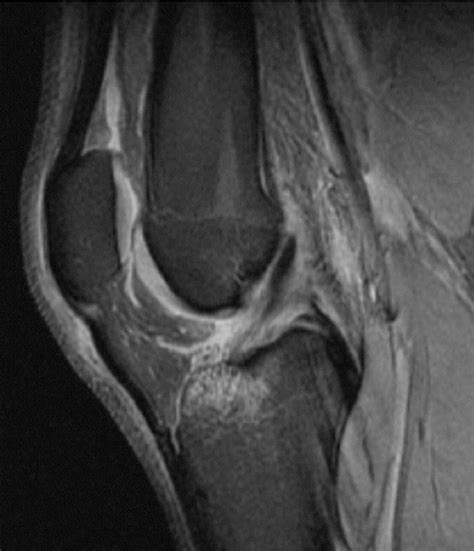

• Order diagnostic imaging tests such as X-rays, MRI, or CT scans to visualize the internal structures of the knee.

Diagnostic imaging is particularly important for identifying the specific structures affected and the extent of the damage. For example, an MRI can provide detailed images of the menisci, ligaments, and cartilage, helping to pinpoint the cause of the internal derangement.